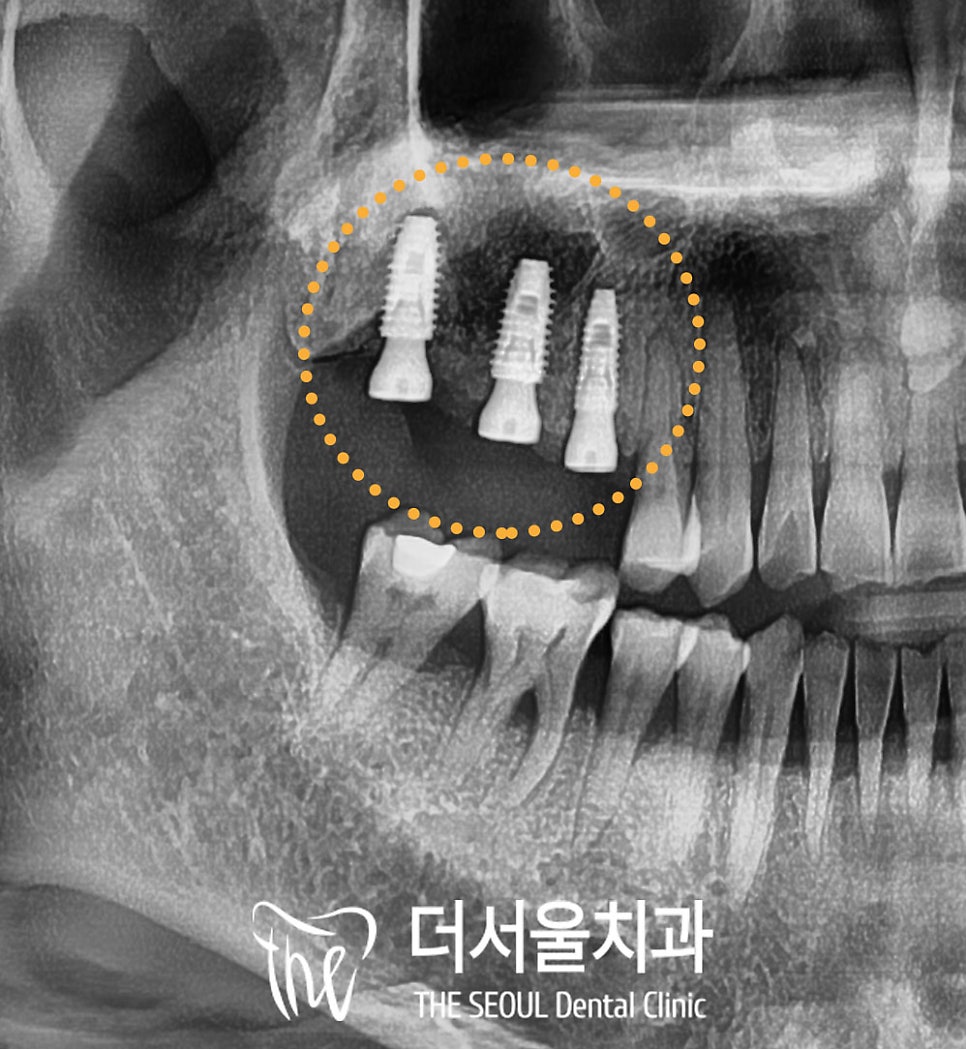

사전 진단 계획 데이터를 바탕으로

예측된 위치에 그대로

수진동 임플란트를 심어드렸습니다.

거상술을 동반하여

뼈가 부족한 부위는 인공뼈도 이식하여

골 유착에 도움을 주었습니다.

4. 최종 결과

상악 우측 어금니

모든 진료가 마무리된 모습입니다.

픽스처 간의 간격도 적절하고

70 이상의 단단한 고정 수치도

확인하였기에

위쪽에 지르코니아 브릿지를

올려드렸습니다.